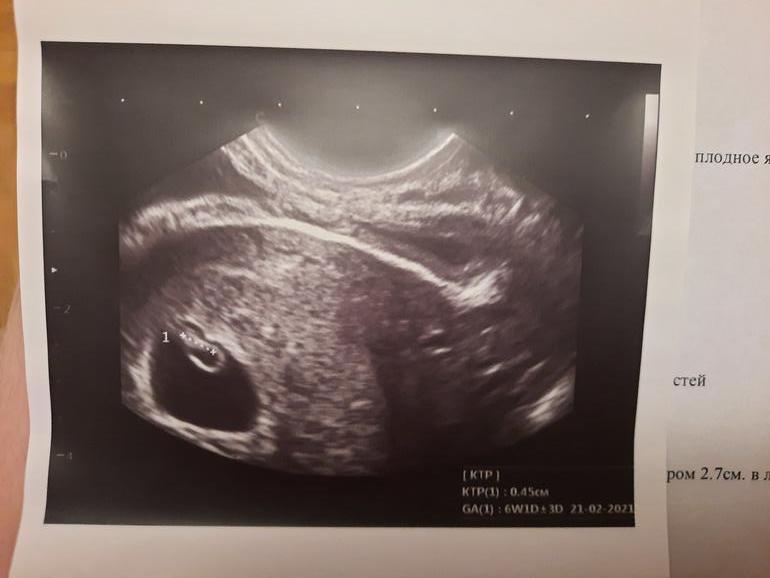

Девочки, кто разбирается, посмотрите, пожалуйста, мальчик или девочка по методу Рамзи? УЗИ вагинальное.